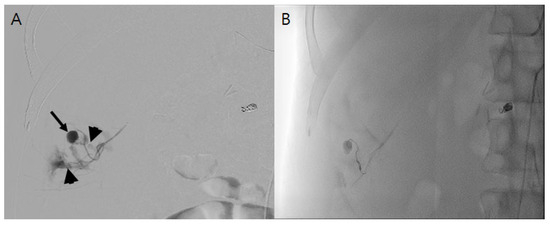

The spontaneous rupture of a subcostal (12th intercostal) artery is exceptionally rare and could be fatal, requiring early diagnosis and treatment. Only one case of intercostal artery (ICA) bleeding in a patient undergoing hemodialysis (HD) has been reported. We additionally describe a 41-year-old [...] Read more.

The spontaneous rupture of a subcostal (12th intercostal) artery is exceptionally rare and could be fatal, requiring early diagnosis and treatment. Only one case of intercostal artery (ICA) bleeding in a patient undergoing hemodialysis (HD) has been reported. We additionally describe a 41-year-old man undergoing HD who presented with a spontaneous hemoperitoneum and shock resulting from a subcostal artery rupture. He initially complained of diffuse abdominal pain and dizziness at the emergency room. His abdomen was bloated, and there was tenderness in the right upper quadrant area. Enhanced computed tomography and arteriography revealed a rupture of the right subcostal artery. After the super-selection of the bleeding artery by a microcatheter, embolization was performed using a detachable coil and gelfoam. In a subsequent arteriogram, additional contrast leakage was no longer detected, and his blood pressure was restored to normal. The patient was discharged without any sequelae. He was followed up at our HD center without recurrence of ICA bleeding. To the best of our knowledge, this is the second case in the English literature documenting a spontaneous ICA rupture in a patient undergoing HD. This case indicates that injury to ICA should be suspected when patients undergoing HD complain of abdominal or chest pain and dizziness, although it is very rare. Full article